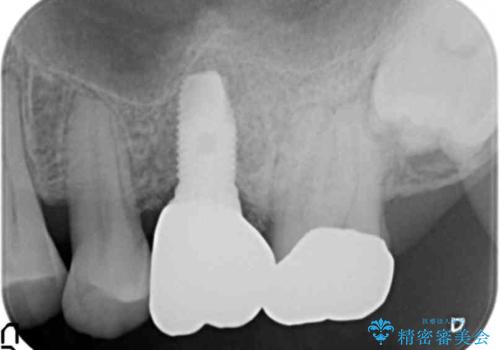

- 奥歯のインプラントをご希望し、来院された患者様です。

精査したところ上顎骨の厚みが薄かったため、ソケットリフト(上顎洞底挙上術)を併用してインプラント治療を行いました。

インプラントの種類:スプライン ツイスト (保証期間:5年)

クラウンの種類:ベレッツァクラウン (オールセラミック)

固定様式:セメント固定